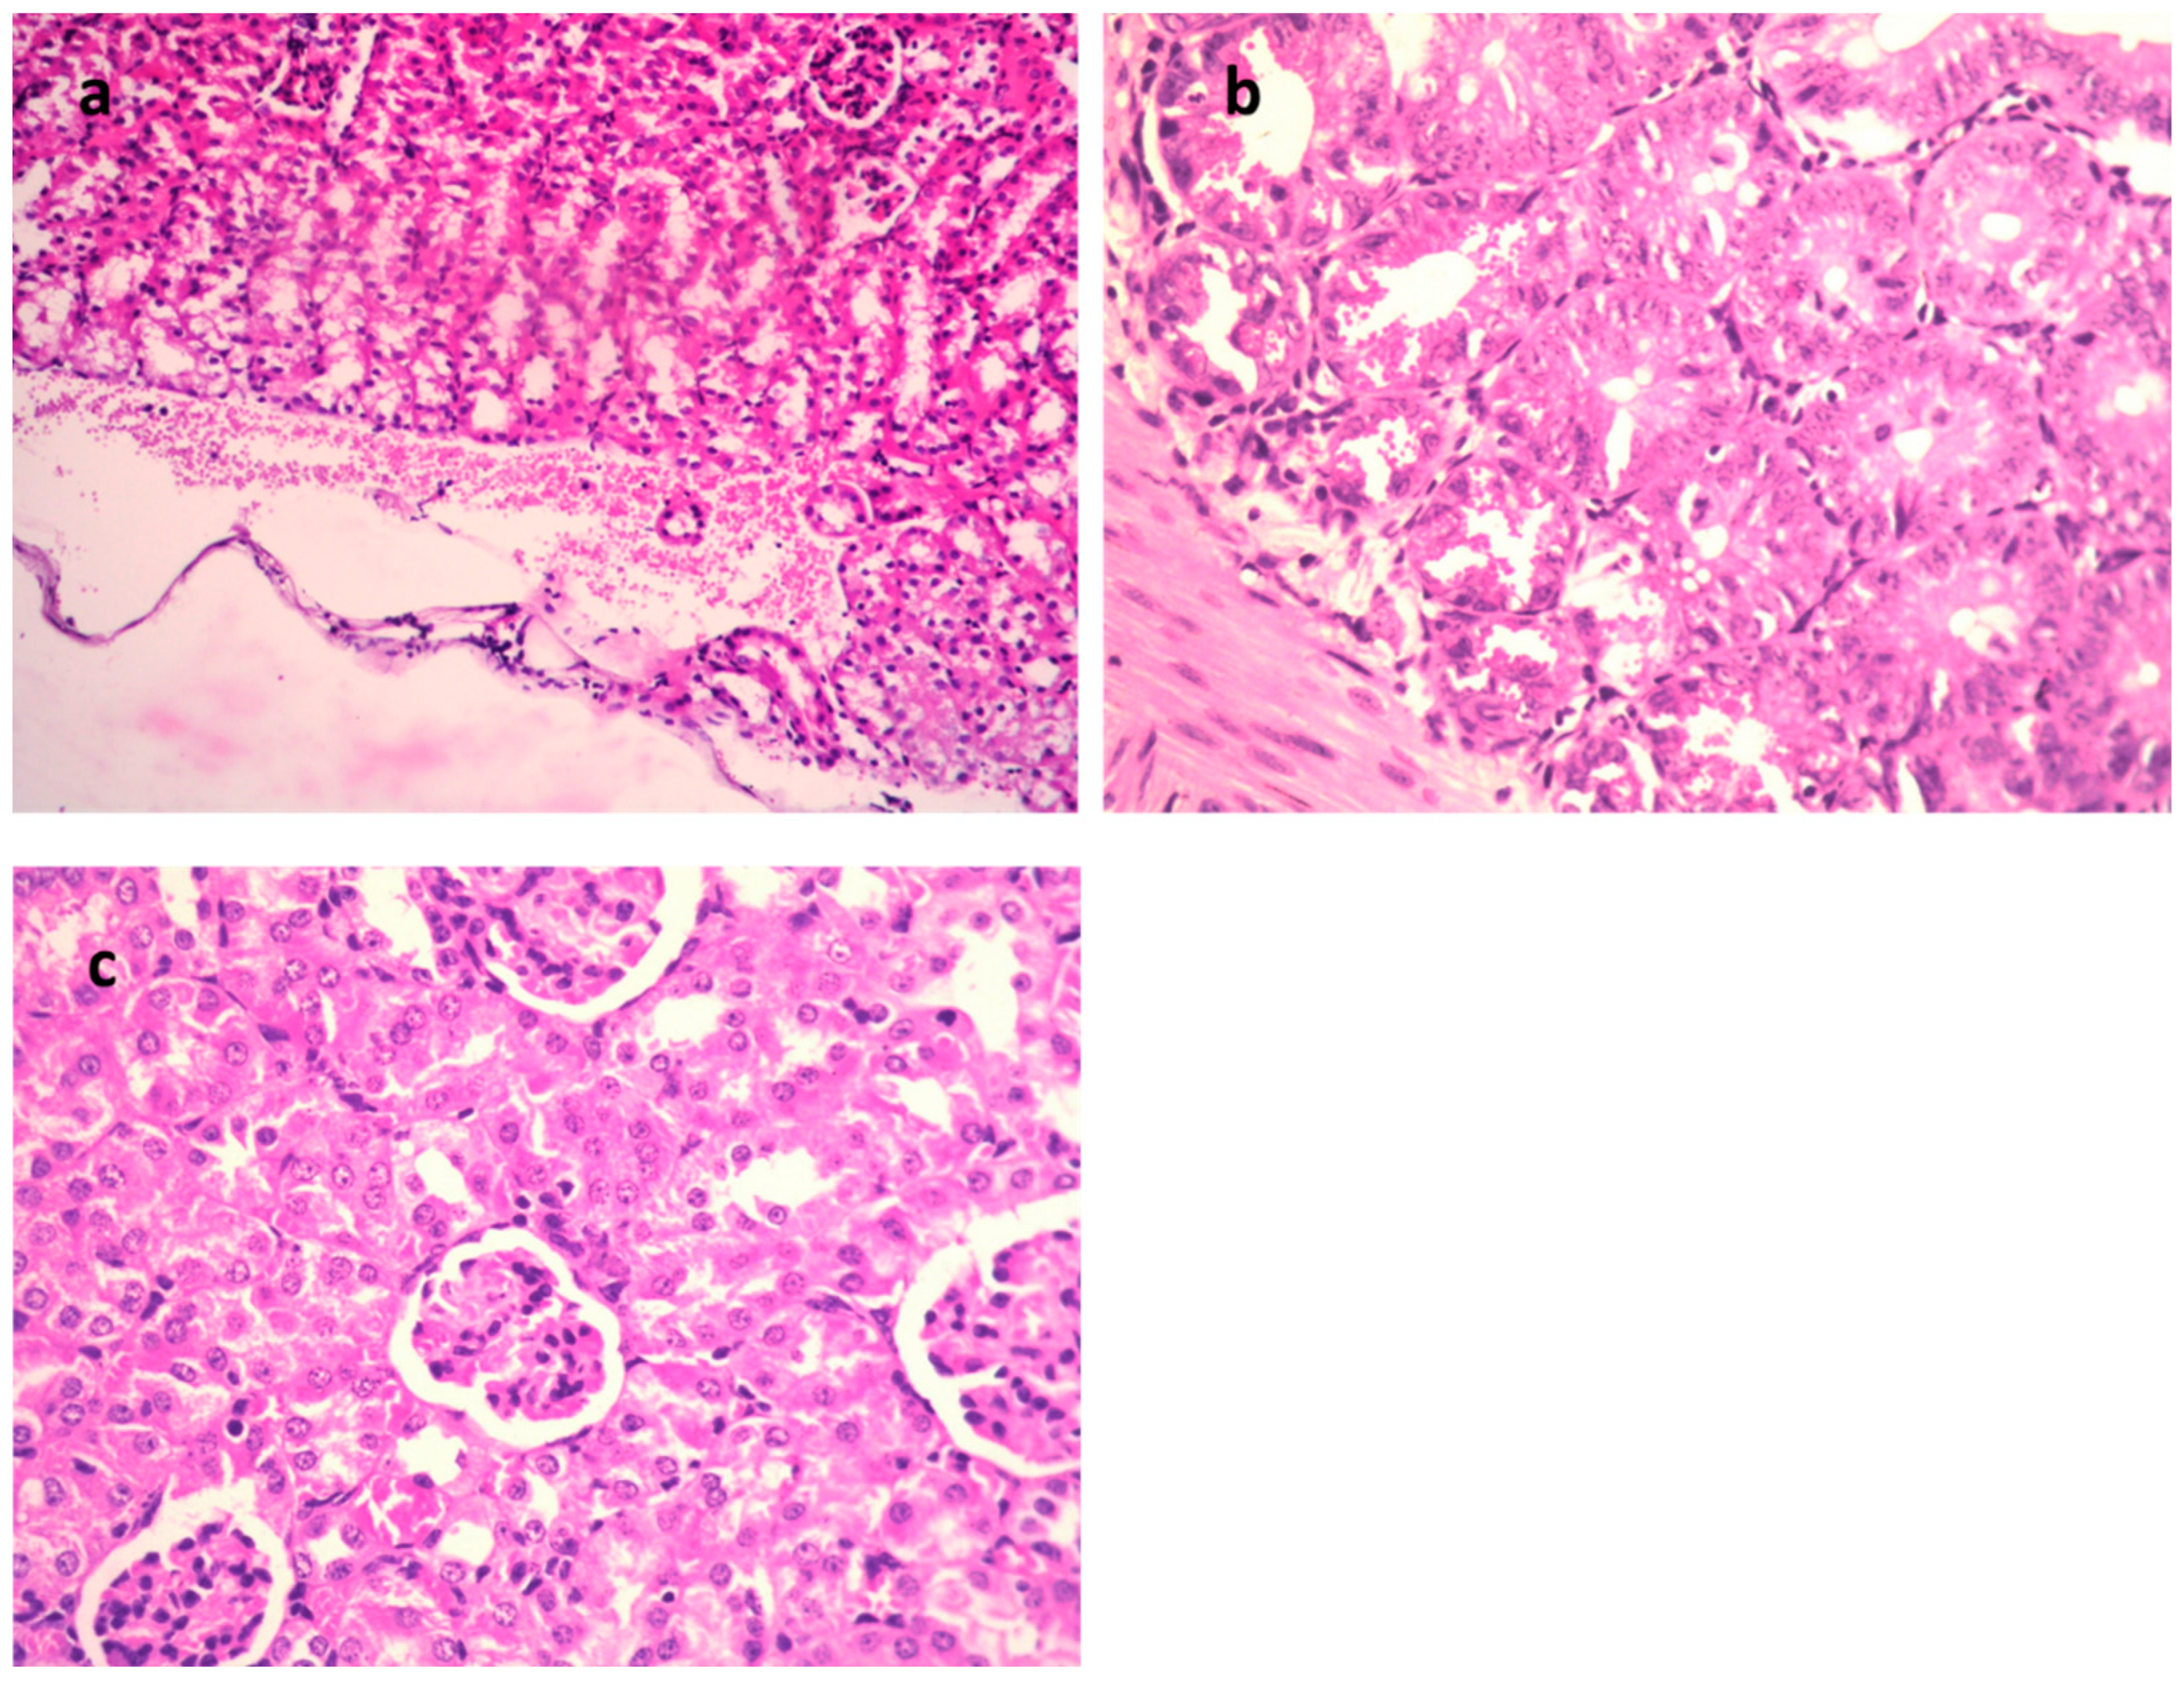

| Thickened interalveolar septa | − | +++ | + | + |

| Perivascular edema | − | +++ | + | − |

| Hemorrhage | − | +++ | − | − |

| RBCs in alveolar lamina | − | +++ | + | − |

| Normal Control Group | Model Group | 9-Methoxyellipticine-Treated Group | Gentamycin (GEN)-Treated Group | |